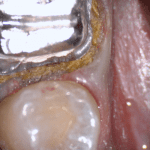

In this clinical video we demonstrate how to scan a molar preparation for the replacement of a crown with recurrent decay and open margins. The molar was root canal treated and the tissue was inflamed. the preparation was imaged and a temporary was fabricated to allow the tissue to heal properly.

The main point of this video is to show how to capture the contacts of the adjacent teeth and the deep marings